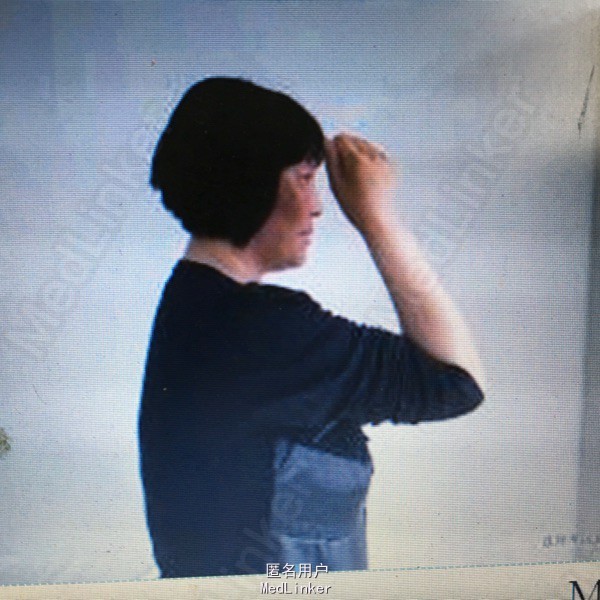

女性患者,43岁,因交通伤致右尺桡骨开放性骨折,当地医院行清创、骨折切开复位内固定术,术后尺侧切口反复红肿、流脓,经换药治疗4个月前臂仍疼痛、畸形、功能受限,X线片(A, B);第1阶段手术探查明确诊断(感染范围、程度及细菌种类),桡骨重新复位、内固定、恢复力线、间接稳定尺骨,尺骨骨折断端清创、抗生素骨水泥占位器置入(C),术后X线片(D, E);全身及局部应用敏感抗生素;第2阶段膜诱导技术修复骨缺损;切开诱导生成的生物膜,取出骨水泥占位器,钢板固定骨折(F, G);髋臼锉取骨技术获取粉碎松质骨、皮质骨混合颗粒,锁定钛板内固定和愈合片子(H, I)